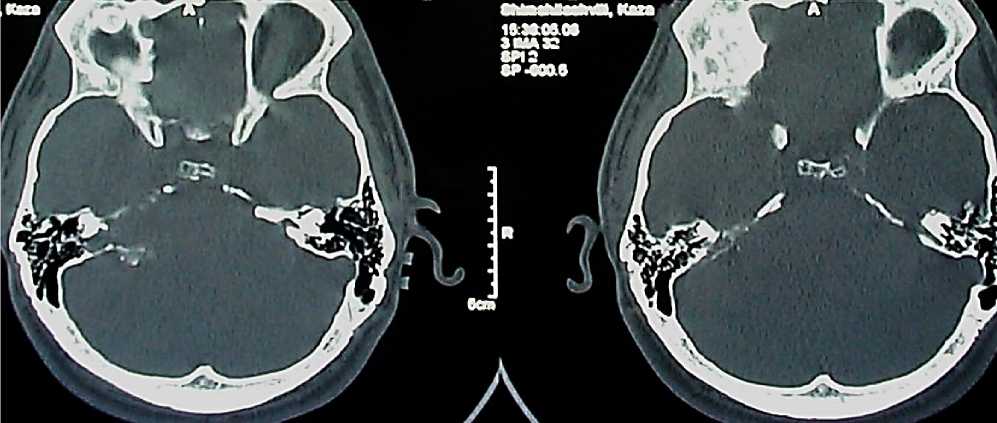

С целью определения диагностических возможностей КТ в выявлении различных КТ характеристик опухолей VIII нерва и определения ценности полученных данных, для суждения об истинных размерах опухоли проанализированы КТ картина 79 больных с ВШ (Рисунок 1).

Рисунок 1. КТ головного мозга в костном режиме

Обследование проводилось на компьютерном томографе с коллиматором от 1,5 до 3 мм. Голова пациента располагается в положении антефлексии таким образом, что применяются аксиальные срезы под углом Гентри до 30 градусов к орбитомеатальной линии (линия от нижней границы орбиты до верхней границы наружного слухового прохода) почти параллельно к основанию черепа. Толщина срезов составляла 1-2 мм с высоким контрастным разрешением и со значением шкалы плотности + 3000 Н.Е. (костные окна).

Для визуализации костных структур внутреннего уха были сделаны тонкие срезы до 1,5 мм по шкале плотности через пирамиду височной кости. На этих КТ срезах могут быть обнаружены полукружный канал с ампулами, crus commune, вестибулярный аппарат, внутренний слуховой канал, также, как и мягкотканые образования. Aquaductus vestibule при этом обнаруживается в своем дистальном, широком участке пути в области saccus endolimphaticus (Рисунок 2).